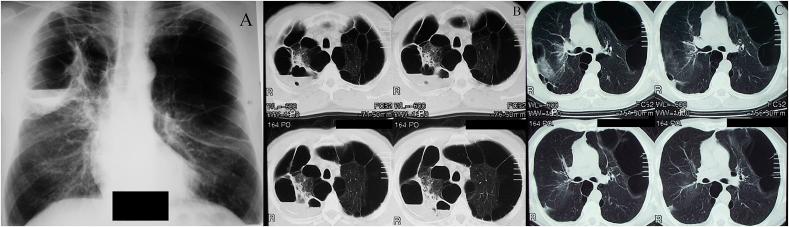

Bullae formation on a cystic background is still not described thoroughly. This clinical case aims to improve this situation and describes the combination of multiple cysts with vascular malformation, giant bullae (2/3 of the left hemithorax and 1/2 of the right hemithorax) with suppuration in a 50-year-old smoker. Before surgery, treatment for chronic obstructive lung disease (COPD) was administered without a positive outcome. Bullectomy was subsequently conducted and histopathological data revealed vascular malformation causing microinfarctions in pulmonary parenchyma, cystic degeneration and tuberculosis. Although it became possible to establish a final diagnosis due to histology, the need for surgical treatment was clear from clinical and x-ray evidence. Such instances as the one presented in this case report should assist with improving our knowledge about bullae in combination with cysts in the lungs because they provide additional context in a clinical setting.

摘要

囊性背景下大疱的形成仍未得到充分描述。本临床病例旨在改善这种情况,并描述了一名50岁吸烟者中多个囊肿与血管畸形、巨大肺大疱(左半胸的2/3和右半胸的1/2)合并化脓的情况。手术前,给予了慢性阻塞性肺疾病(COPD)治疗,但未取得阳性结果。随后进行了肺大疱切除术,组织病理学数据显示血管畸形导致肺实质微梗死、囊性变和肺结核。尽管通过组织学得以做出最终诊断,但从临床和X线证据来看,手术治疗的必要性是明确的。本病例报告中呈现的此类病例应有助于增进我们对肺部大疱合并囊肿的认识,因为它们在临床环境中提供了更多背景信息。